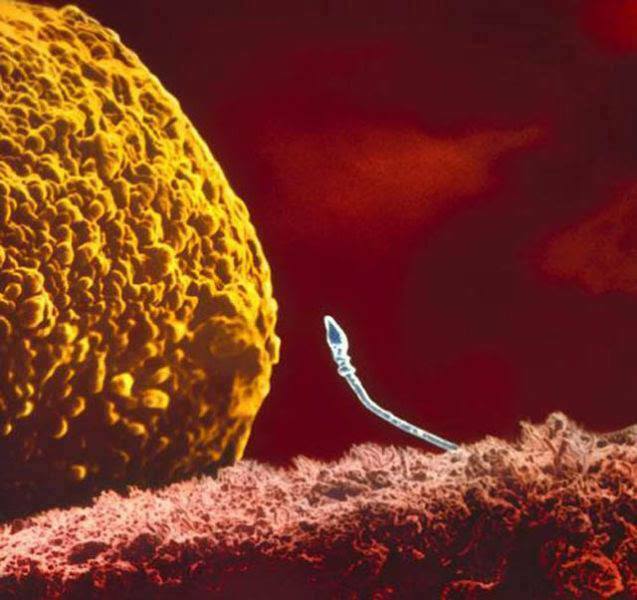

3.精子終於遇見了卵子,它們是否能一起創造愛的結晶呢?

4.兩個精子試圖要突破卵子並準備結合,究竟誰會成功呢?緊張緊張!